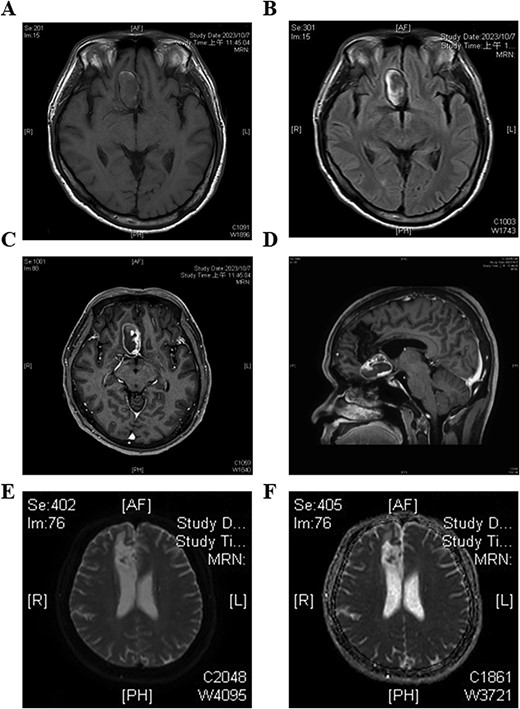

Blood tests revealed elevated glucose (152 mg/dl) and alanine transaminase (ALT) levels (116 U/L), while other parameters were normal. Brain magnetic resonance imaging (MRI) showed a giant thrombotic aneurysm in the proximal A2 segment of the right ACA near the anterior communicating artery (A-com). The aneurysm was completely occluded, and a chronic infarction was present in the territory of the right ACA (Fig. 1).

Preoperative brain magnetic resonance imaging (MRI) of the patient reveals a giant aneurysm in the right frontal area. (A) T1-weighted image shows the mass as hypointense. (B) T2-FLAIR image shows hypointensity in the center with peripheral hyperintensity. (C, D) Contrast-enhanced T1 images demonstrate peripheral contrast stasis around the mass, with no enhancement observed in the distal right anterior cerebral artery (ACA). (E, F) Diffusion-weighted image (DWI) and apparent diffusion coefficient (ADC) images show infarction in the areas supplied by the right distal ACA.